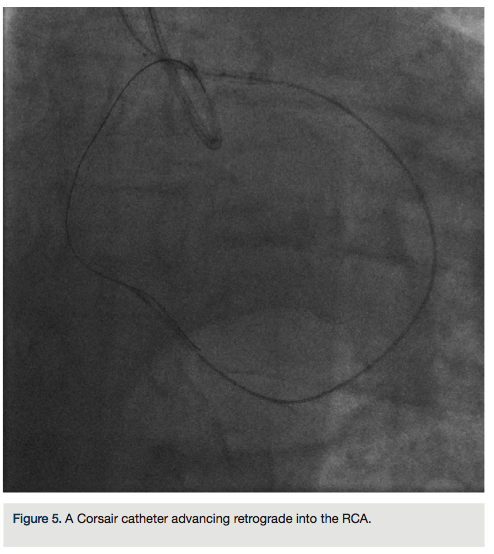

heparin to achieve an ACT >300, we went from the left system with a Runthrough wire (Terumo) and an over-the-wire balloon, using the workhorse wire to wire the circumflex. We then changed to a retrograde crossing wire, the Asahi Fielder FC (Abbott Vascular), to wire into the collateral going to the distal RCA (Figure 3) and were able to advance in a retrograde fashion all the way into the true RCA (Figure 4). We backed out the 1.5 mm balloon and trapped it in the guide with a 2.5 x 20 Emerge (Boston Scientific), inflated to 16 atmospheres. We exchanged out initially for a Corsair catheter (Asahi Intecc) and advanced retrograde into the

RCA (Figure 5). Using a Pilot wire (Abbott Vascular), we were able to advance in a retrograde fashion into the RCA guide, but the Corsair catheter was not long enough to go all the way (a 135 cm catheter was inadvertently opened instead of the 150 cm). Therefore, we trapped the Pilot wire into the RCA guide with a 2.5 x 20 Emerge balloon after removing the antegrade wire (the Pilot wire is hydrophilic; therefore, one needs to exercise caution when trapping). We removed the 135 cm Corsair and advanced a 150 cm Corsair retrograde into the RCA guide. We then removed the Pilot wire through the Corsair, running retrograde from the left guide to the right guide. We rewired the Corsair in an antegrade fashion, rather than